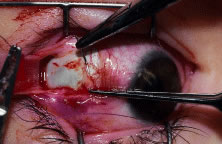

RESECTION PROCEDURE: FORNIX INCISION

This procedure is a resection of a lateral rectus muscle. The approach to the rectus muscle to be resected is similar to that of the recession. The limbus is grasped with a Lester forceps. The globe is rotated up and away from the muscle to be resected. The conjunctiva is incised, and the rectus muscle is grasped with a Stevens' hook that is replaced with a Jameson hook. The Tenon's tissue and intermuscular septa are cut and reflected onto the Jameson hook. The intermuscular septa are cut with a Westcott scissors. The rectus muscle tendon is then suspended between the Jameson muscle hook (Fig. 38).

|

A fine-wire spatula-tip needle is woven through the muscle or tendon. Care is taken to avoid the anterior ciliary vessels on the orbital surface of the muscle (Fig. 39). The resection effect is achieved by measuring the location of the transverse suture from the posterior portion of the Jameson hook at the insertion to a predetermined point on the muscle tendon. Various locations can be used as reference points. This measurement can be taken from the anterior, middle, or posterior portion of the Jameson hook under the muscle. Periodic review of the effects of the operation will determine the amount of surgical correction that is achieved for each surgeon's individual technique. The suture is passed back through the tendon on the origin of the muscle side of the transverse suture. The suture is secured to the tendon with double-throw lock knots (Fig. 40). The muscle is clamped with a fine-tipped vascular clamp (Fig. 41A). A vascular clamp is used because it minimizes the crush damage to tissue that is held in the clamp. Care is taken not to include the transverse suture or any of the lock knots in the clamp. The clamp is stabilized on the drape with a towel clip (see Fig. 41B). A Stevens' hook is used to pull the conjunctiva and anterior Tenon's tissue away from the muscle, and a Westcott scissors is used to cut the muscle free from its insertion (Fig. 42). The muscle stump that is to be resected is grasped with forceps and elevated from the clamp. The resected tendon is then cut free from the clamp with a Westcott scissors (Fig. 43). The sutures are pulled away from the jaws of the clamp by the assistant so that they are not cut. A wet-field cautery is used to cauterize the stump of muscle that is held in the clamp (Fig. 44). The muscle insertion is grasped with a locking Castroviejo forceps in the center of the insertion. Each needle is passed from the upper or lower (for a vertical rectus, medial or lateral) pole of the insertion to exit near the center of the old insertion. The intrascleral bite is made in sclera that is just anterior to the insertion. This location is used to allow the needle to pass through the thickest portion of the sclera (Fig. 45). At the midpoint of the insertion, the tip of the needle is brought out of the sclera and the needle is regrasped and passed through the central portion of the muscle tendon on the origin side of the previously placed transverse suture (Fig. 46). A double-throw knot is tied, and the knot is pinched by the surgeon's index finger and thumb (Fig. 47A and B). The muscle clamp is removed, and the knot is pulled down to the muscle by elevating the suture and snugging it down in a stepwise fashion. Two or three additional square knots are added to secure the muscle to the new insertion (Fig. 48). The muscle is inspected to verify that Tenon's tissue is not drawn into the insertion. The knot is trimmed, and conjunctiva is reposited over the muscle with a Stevens' hook (Fig. 49).

|

|

|

|